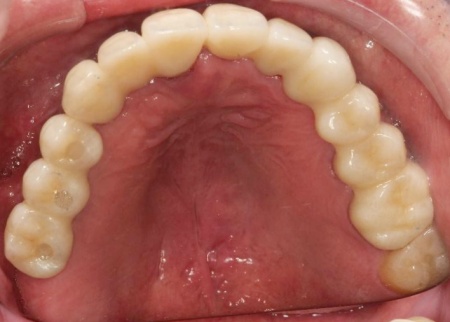

治療後

インプラントが骨にしっかりとなじんだことを確認したら、白くて強度の高い人工歯「ジルコニアクラウン」を装着しました。

また、インプラント治療と並行して、合わなくなっていた被せ物・詰め物・既存のインプラントを作り替えます。

左上奥歯は、装着されていた金属の古い詰め物を外し、白い樹脂を直接詰める「ダイレクトボンディング」で修復しました。